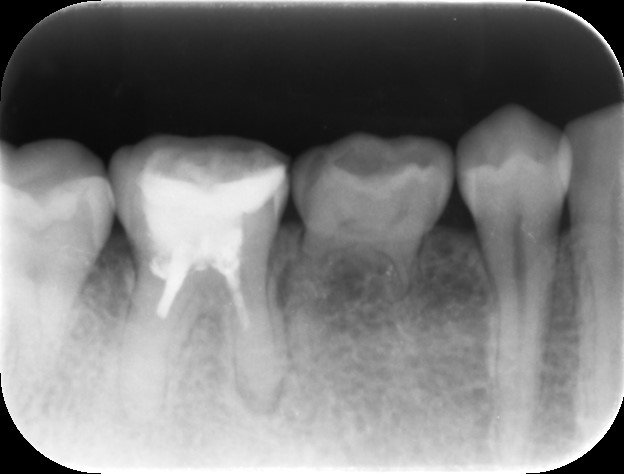

| 治療前レントゲン | 治療前CT |

|---|---|

| 治療前レントゲン |

|---|

| 治療前CT |

再根管治療12か月後のレントゲンおよびCT画像です。根尖病変は消失し、歯槽骨は完全な再生を認め治癒しています。